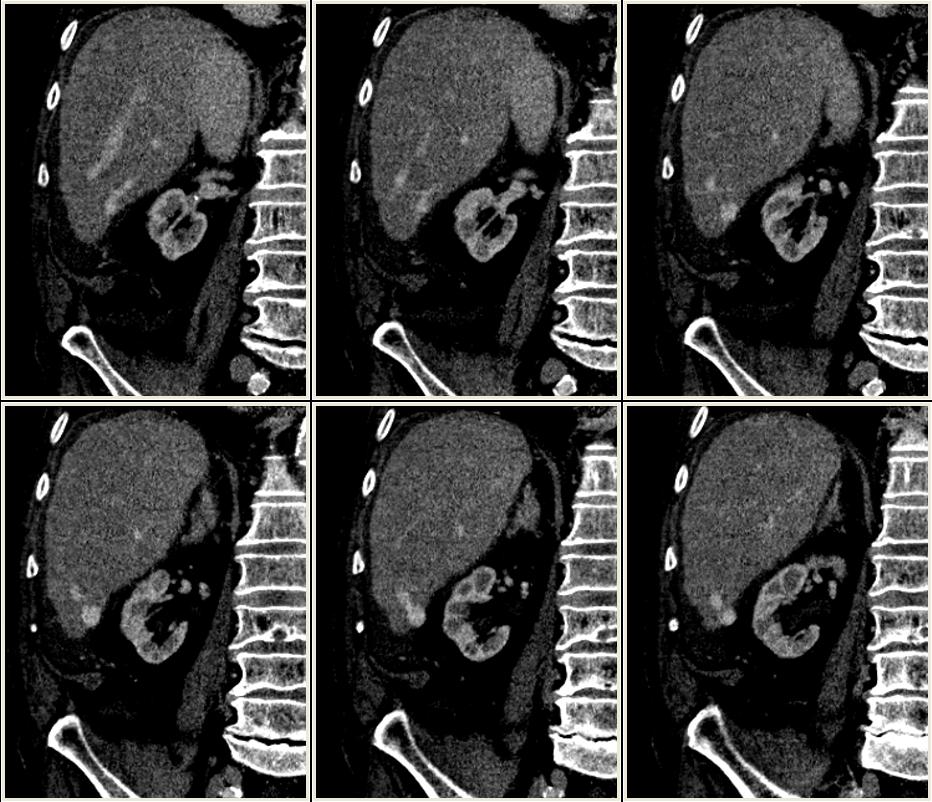

A máj VI-os szegmentumában egy ovoid, a kontrasztanyagot a porta és a májvénákban látott mértékben halmozó képlet, melyhez két vaskosabb értörzs fut. Az egyik a jobb oldali portális ágból, a másik pedig a jobb oldali hepaticus vénából.

= veno-venosus malformatio